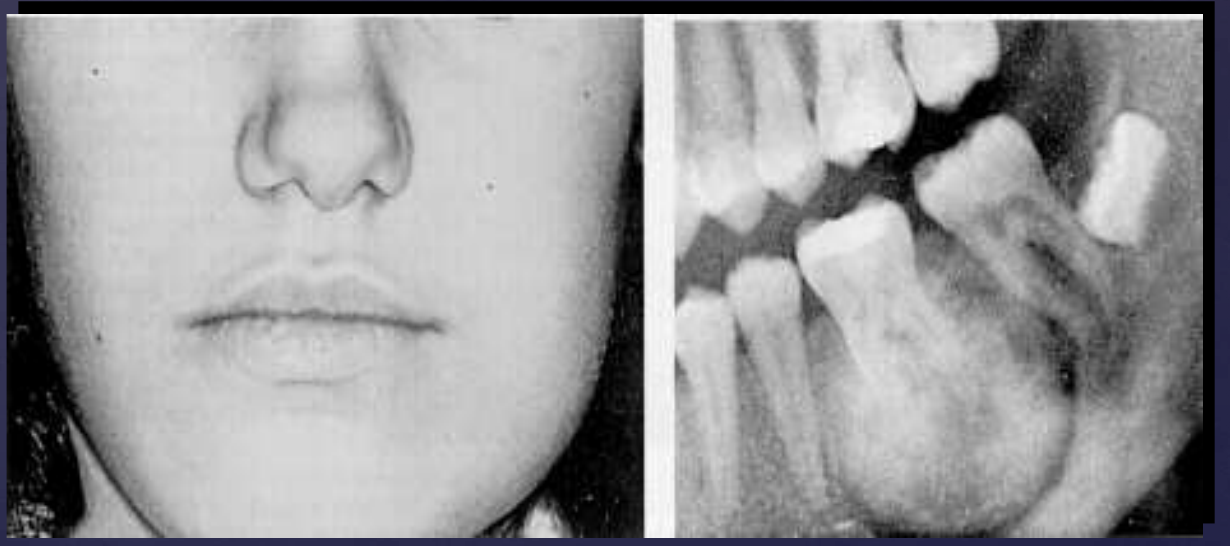

ameloblastoma

% of Unicystic Ameloblastomas are diagnosed between ages 10-20

50%

Unicystic Ameloblastomas have a predilection for what location?

posterior mandible

radiographically, Unicystic Ameloblastomas often mimic what?

dentigerous cysts

Unicystic Ameloblastomas

expansion/thinng ext. oblique ridge